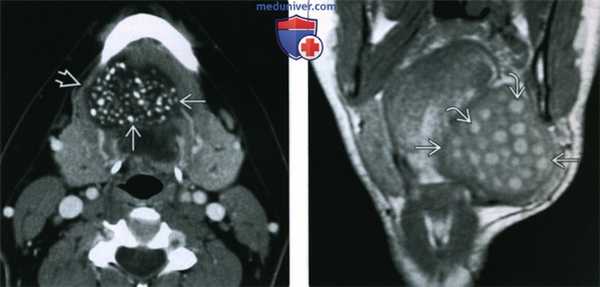

2. КТ при дермоиде и эпидермоиде полости рта:

• КТ без контрастирования:

о Дермоид: содержимое жировой плотности, жидкость средней плотности, кальцификаты (< 50%)

о Эпидермоид: жидкостная плотность без комплексных элементов

• КТ с КУ:

о Возможно незначительное накопления контраста в стенках кисты

о При наличии минимальных дополнительных компонентов в дермоидной кисте ее может быть невозможно отличить от эпидермоидной кисты

(Слева) КТ с КУ, аксиальная проекция. Располагающееся парамедианно образование подъязычного пространства. Образование имеет четкие контуры и располагается медиальнее челюстно-подъязычной мышцы. Определяются множественные кальцификаты и участки пониженной плотности, характерные для эпидермоидной кисты.

(Справа) МРТ Т1ВИ, коронарная проекция. Крупная дермоидная киста подъязычного пространства, смещающее челюстно-подъязычную мышцу в латеральную сторону. Округлые участки гиперинтенсивного сигнала представляют собой жировую клетчатку. Они характерны для дермоидной кисты и позволяют отличить ее от эпидермоидной кисты, ранулы или лимфатической мальформации.